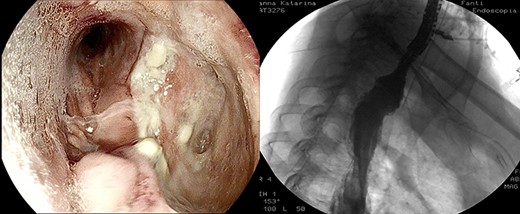

Anastomotic dehiscence was conservatively treated by EVAC therapy, placing the Esosponge in pleural space via an overtube (Fig. 2).

EVAC uses the main principle of negative pressure wound therapy by decreasing bacterial contamination and local edema while promoting perfusion and granulation tissue formation. The sponge can be placed in either an intraluminal or an intracavitary position across an internal fistula opening, using the overtube with a designated pusher. In our case, the sponge was always set inside the cavity because of the large size of the collection.